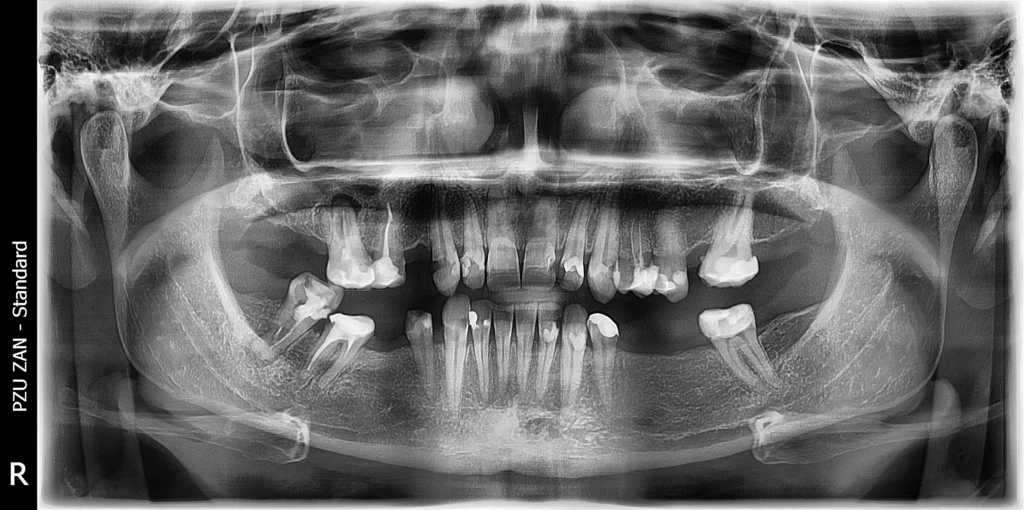

After a thorough clinical examination and advanced 3D CBCT imaging, we carefully analyzed her condition and created a fully personalized treatment plan.

The solution included a combination of dental implants, crowns, and bridges—designed to restore both function and aesthetics in the most natural way possible.

In the first phase, we placed six dental implants using computer-aided surgical guides. This technology allowed us to achieve exceptional precision, ensuring optimal positioning, stability, and long-term success of each implant.

Following a healing period of 4 months, during which complete osseointegration occurred, we moved to the next stage. The patient was fitted with a prototype “try-on” smile, giving her the opportunity to preview the final result and ensure complete satisfaction with the shape, size, and appearance.